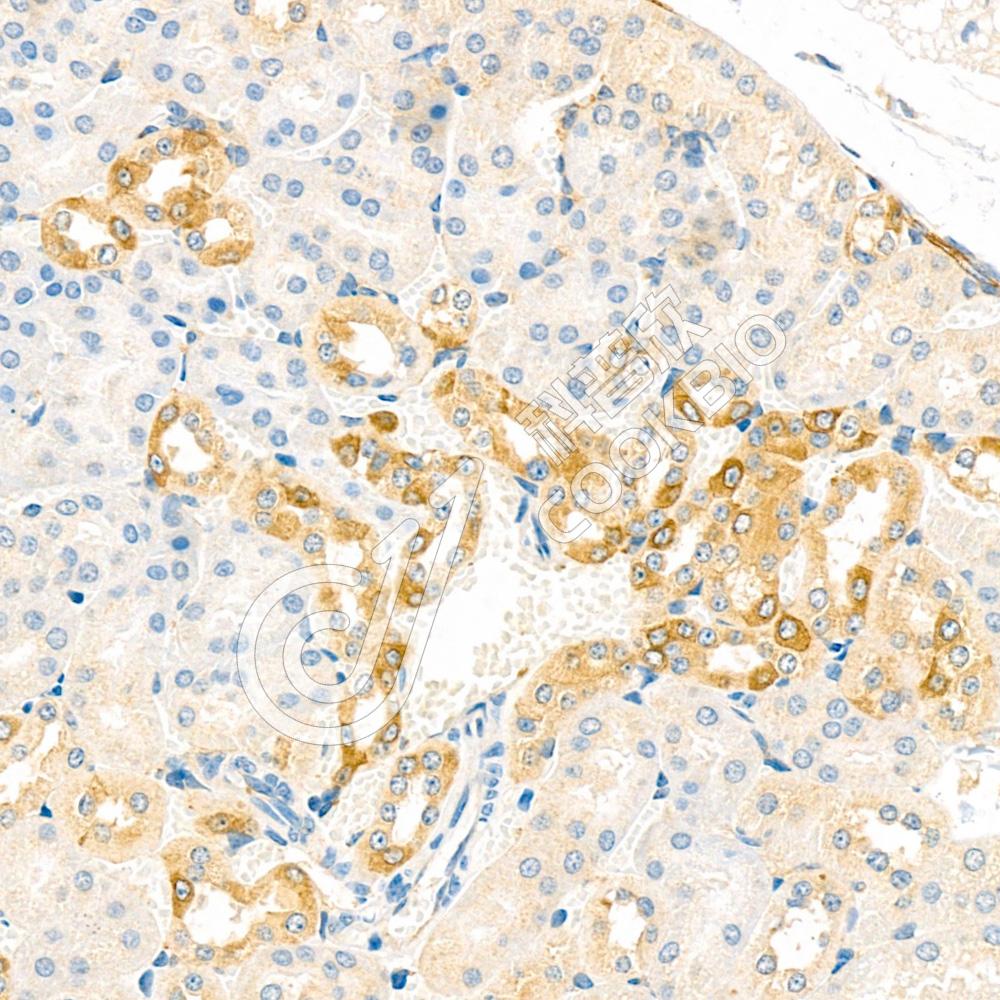

IHC检测ARSK蛋白(货号 K1334800).

样品: 小鼠肾, 4%多聚甲醛 (货号KSG1101) 固定12-24小时.

抗原修复: 柠檬酸抗原修复液(干粉, pH 6.0) (KSG1201), 98℃, 20分钟.

—抗: 1: 2500稀释, 4℃ 孵育过夜.

二抗: S-vision免疫组化多聚二抗(山羊抗兔),即用型 (货号KB3906), 室温孵育20分钟.